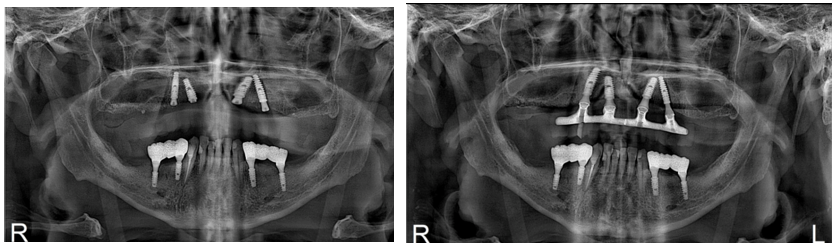

Após três meses, período adequado da osseointegração e a verificação radiográfica, foram realizadas todas as etapas referentes a prótese, dentre elas: reabertura, escaneamento, moldagem, registro de mordida, prova dos dentes e instalação do protocolo.

A guia cirúrgica foi removida, o torque foi conferido e foi colocado o tapa-implante. Associado a isso, também foi realizada a verificação dos implantes por meio de radiografia periapical.

Posteriormente, após o acompanhamento e o tempo pré-determinado, foi realizada a reabertura e a colocação de cicatrizador a fim de realizar a readequação dos tecidos moles peri-implantares. Nesta sessão, as demais etapas clínicas propostas já estavam finalizadas.

Por fim, o tratamento finalizou com a carga precoce dos implantes que culminam na instalação dos pônticos de zircônia sobre os implantes.